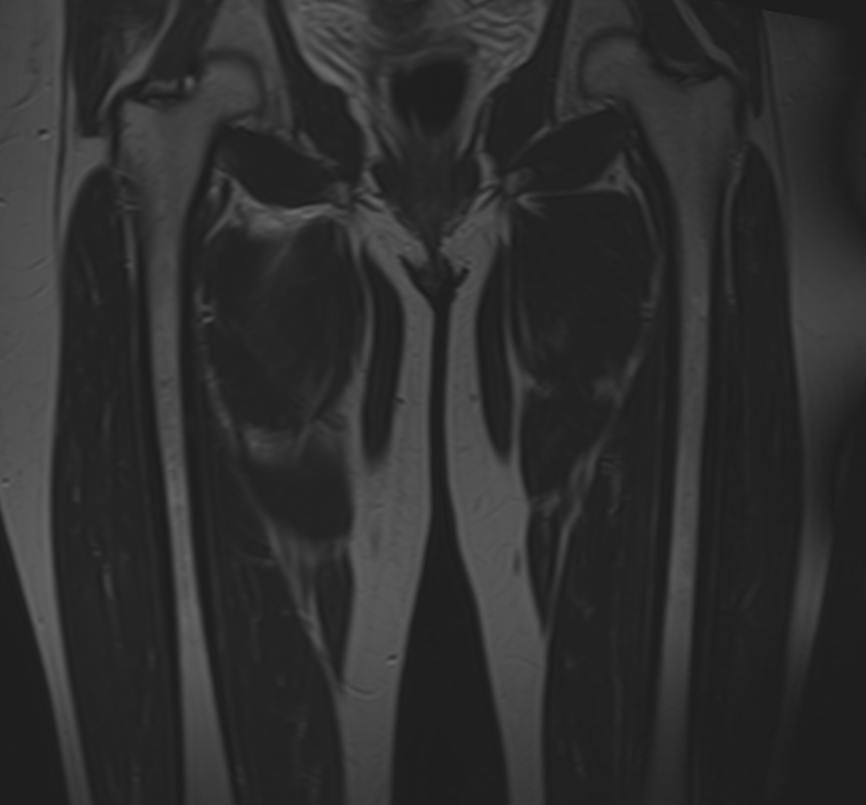

Магнитно-резонансная томография применяется для обследования мягких тканей верхних и нижних конечностей, включая кожу, подкожно-жировую клетчатку, мышцы, фасции, межфасциальные пространства, сухожилия, связки, сосудистую систему, лимфоузлы и лимфатические протоки, нервные волокна, надкостницу и костный мозг.

Кроме того, имеет значение показатель индукции магнитного поля томографа. Наша клиника оснащена современным высокопольным томографом последнего поколения TOSHIBA VANTAGE TITAN 1,5 Тесла. Высокая индукция магнитного поля обеспечивает повышенную четкость изображений при обследовании мягких тканей конечностей. За счет послойного сканирования в различных плоскостях с шагом от 1 мм и последующего преобразования данных в объемные изображения томограф обеспечивает выявление мельчайших изменений в тканях. Это позволяет проводить диагностику различных заболеваний на самых ранних стадиях.

- Воспалительные заболевания (миозиты, артриты, тендиниты, тендовагиниты и др).

- Гнойные процессы (инфильтрация, флегмона, абсцесс).

- Травматические повреждения (растяжения, разрывы мышц, связок, сухожилий)